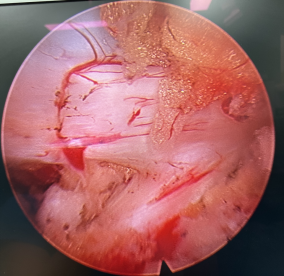

內(nèi)鏡下可以清晰顯露硬膜及神經(jīng)根

脊柱外一科 (骨一科)程才主任主刀,應(yīng)用局部浸潤麻醉,在內(nèi)鏡大通道下進行腰4/5節(jié)段狹窄的單側(cè)入路雙側(cè)椎管減壓,只有一個1cm切口,術(shù)中出血僅20ml,既達到充分的減壓效果,又不影響脊柱的穩(wěn)定性,整個過程不到2個小時。術(shù)后,李奶奶終于能安安穩(wěn)穩(wěn)的睡了一覺,術(shù)后2個小時就能夠自己下地行走。

內(nèi)鏡下腰椎椎管減壓,保留了脊柱的穩(wěn)定結(jié)構(gòu)